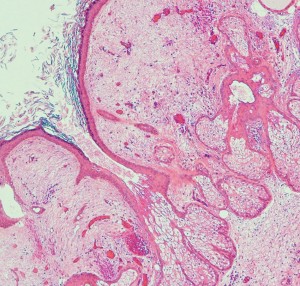

病理所見です

epidermisにhair follicle, sebaseous glandを伴うdermoid cyst 類皮のう胞の診断です。上皮に接する脳組織(これは正常脳組織ではなくて成熟奇形腫の内部にできた脳組織)の内部にgerm cell nest(矢印)が認められました(左下拡大)。mature teratomaにgerminomaが混在するmixed germ cell tumor と診断されました。